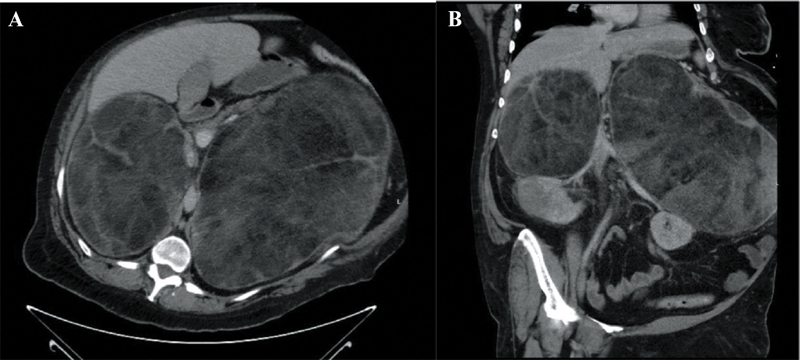

A 41-year-old woman with a history of classic 21-hydroxylase deficiency congenital adrenal hyperplasia, diagnosed in childhood and associated with male reproductive organs, presented after several years without follow-up or medical therapy. She arrived with abdominal pain and anuria, and was in mixed shock from adrenal crisis and septic shock secondary to Escherichia coli pyelonephritis. Initial imaging showed profound enlargement of her bilateral adrenal glands (Figure 1A and B). During hospitalization, she required vasopressor support and renal replacement therapy. Broad-spectrum antibiotics with cefepime were initiated and subsequently narrowed to ceftriaxone, along with stress-dose corticosteroids, resulting in clinical improvement. Hormonal evaluation revealed no evidence of adrenal hypersecretion. She was discharged on hydrocortisone, but declared to have end-stage renal disease requiring ongoing dialysis. Outpatient follow-up with endocrinology and endocrine surgery was arranged to evaluate for bilateral adrenalectomy.

Figure 1

Figure 1. A: Contrast-enhanced computed tomography of the abdomen and pelvis in the axial view revealing large bilateral adrenal masses containing macroscopic fat and soft tissue components. The right adrenal lesion measured 13.6 × 19.2 × 15.6 cm, while the left measured 28.3 × 20.9 × 29.6 cm. These findings were most consistent with adrenal myelolipomas; however, retroperitoneal sarcoma and lymphoma were considered as part of the differential diagnosis. B: Coronal view of the large bilateral adrenal mass.

Initial cross-sectional imaging demonstrated marked, bilateral adrenal enlargement, a finding that can occur in patients with longstanding untreated congenital adrenal hyperplasia (CAH) due to chronic ACTH stimulation. In this patient, the images raised concern for adrenal myelolipomas, benign tumors commonly associated with CAH and characterized radiographically by the presence of macroscopic fat intermixed with soft-tissue elements.1,2 Myelolipomas are typically nonfunctioning but can attain substantial size, leading to mass effect, abdominal pain, or hemorrhage.1,2 The bilateral nature and degree of enlargement in this case are consistent with the recognized propensity of CAH patients to develop multiple and large adrenal myelolipomas, highlighting the importance of imaging in guiding both acute management and long-term surgical planning.